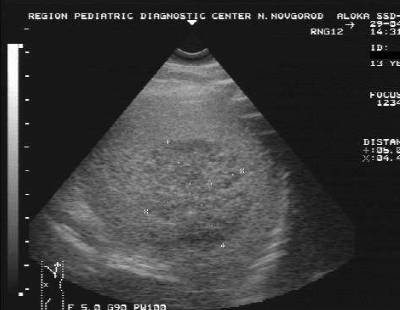

УЗИ

К сожалению, больше никаких данных данная процедура предоставить не может, однако с ее помощью можно точно оценить, кавернозная эта гемангиома или капиллярная, как близко она находится к основным важным сосудам и какую угрозу несет собой для жизни.

УЗИ производят на голодный желудок, а для получения более точных результатов плоскость положения тела пациента может меняться.

Полученные данные являются основой для диагностики, но если их недостаточно, прибегают к помощи более информативного метода – МРТ.